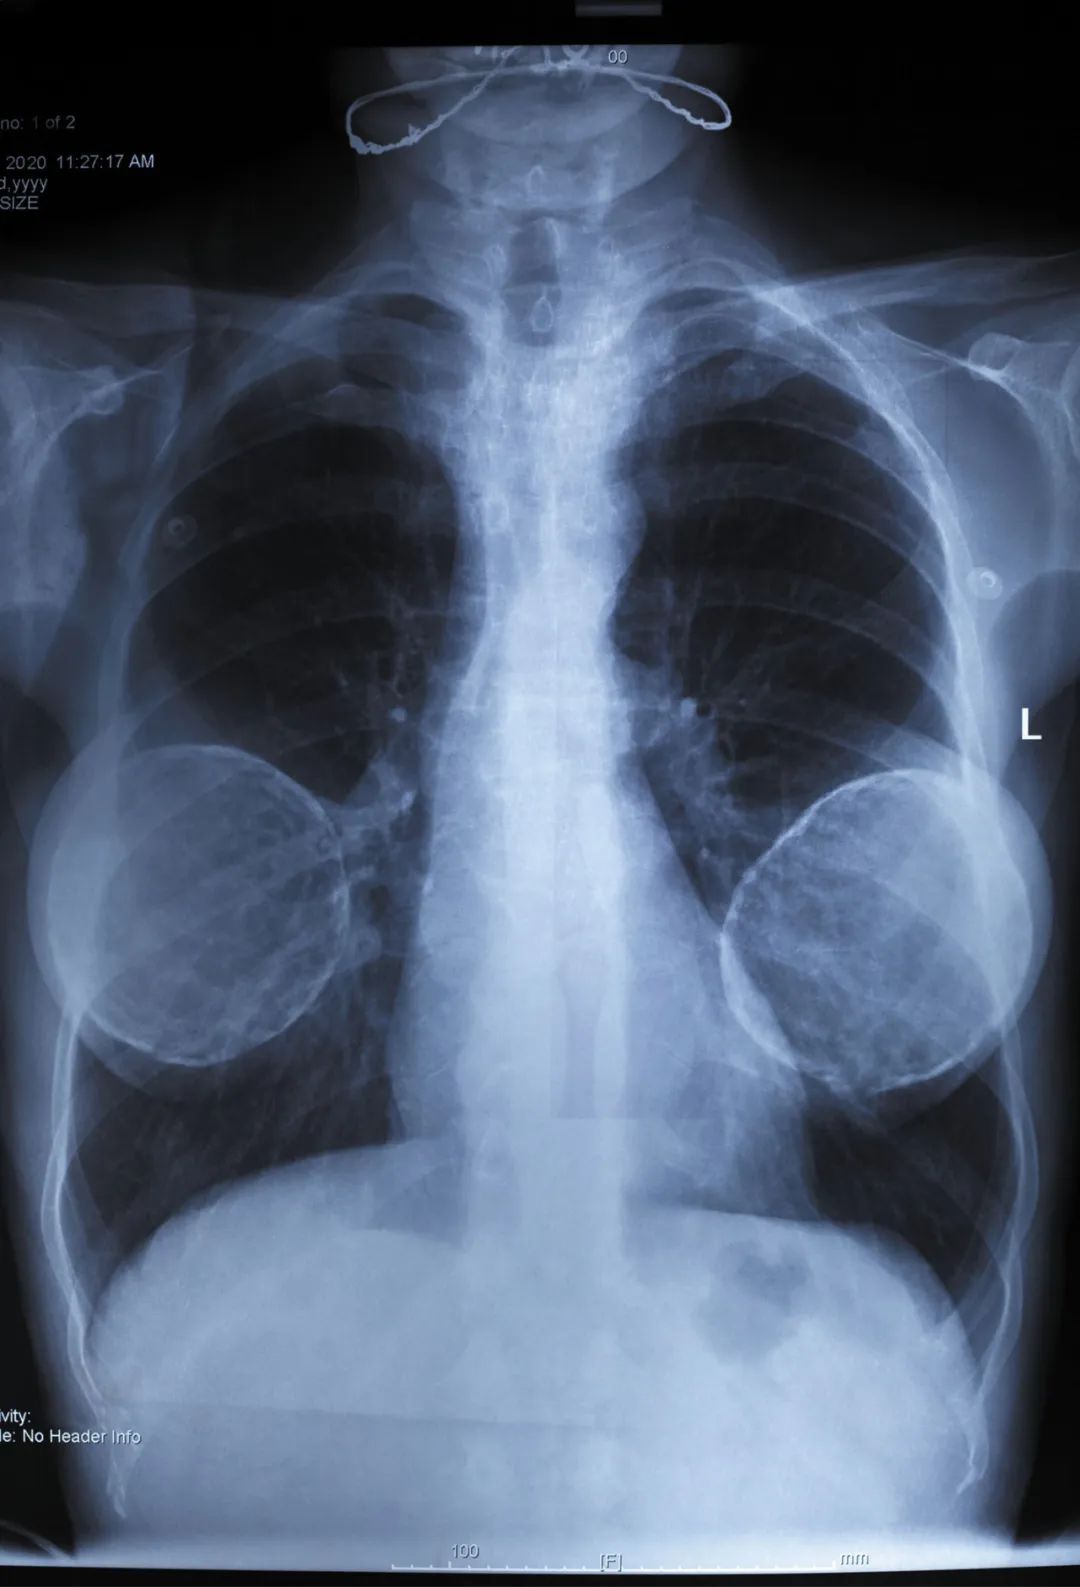

一块移除的已用20年的乳房假体。在其背面(B)可以看到多处孔洞(黑色箭头)以及假体收缩形成的褶皱(白色箭头)。© ResearchGate